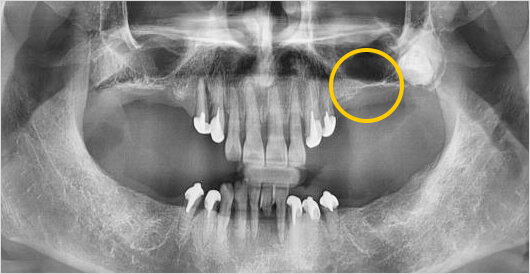

상악동은 코 옆에 있는 두개골의 무게를 줄여주고 숨을 쉴 때

공기 중 노폐물과 코 속의 먼지들을 걸러주는 역할을 하는 빈 공간을 의미합니다.

상악동거상술이란 위 턱 어금니 위쪽에 위치한 상악동을 위로 올려준 후 빈공간에 뼈를 이식하여

임플란트를 식립할 공간을 확보하는 고난이도 수술이기 때문에 충분한 시술경험과 노하우가 있는

병원에서 수술 받으셔야 합니다.

고난이도 임플란트 (상악동 거상술) 수술 전

고난이도 임플란트 (상악동 거상술) 수술 후